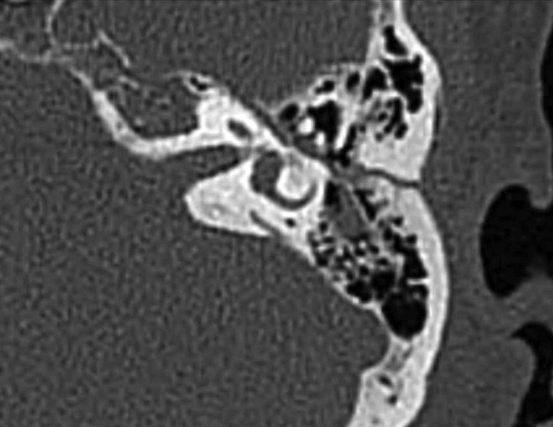

문 2. 58세 남자가 자전거를 타다 넘어져 두부 외상을 입은 뒤 응급실로 내원하였다. 환자는 dizziness를 호소하고 있었으며, 영상검사에서 다음과 같은 소견이 관찰되었다. 이에 대해 맞지 않는 설명은?

문 2. 답

해설 내이에 손상을 초래하는 외상은 이차성 양성돌발두위현훈의 가장 흔한 원인이다.

참고 문헌: 대한평형의학회. 임상평형의학:어지럼과 현훈. 2판. 서울: 범문에듀케이션;2017. p.265-6.